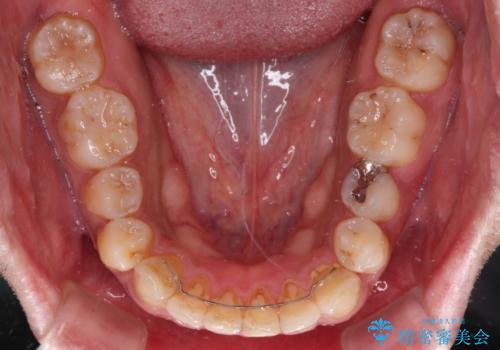

破折して抜歯が必要となった歯の後ろの歯は、根管治療が必要な状態であったので、根管治療を行い、矯正治療後にインプラント部の補綴治療と同時にセラミッククラウンを装着しました。

矯正治療以外に費用負担がかかることになりましたが、気になるところ全てを処置することができ、患者様には大変満足していただきました。